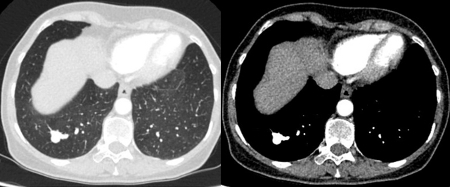

[Figure caption and citation for the preceding image starts]: Computed tomography (CT) showing two left lower lobe peripheral nodules (one slightly spiculated and the other with smoother margins) in a patient presenting with fever, high inflammatory serum markers, and blood cultures confirming Streptococcus intermedius. Both nodules completely resolved following a course of linezolid, consistent with septic emboliFrom the collection of Dr George Tsaknis, MD, PhD, FRCP(London), MRQA, MAcadMEd, PGCert; used with permission [Citation ends].

[Figure caption and citation for the preceding image starts]: Computed tomography (CT) showing a left upper lobe peripheral elongated nodule, with contrast enhancement and a clear feeding and draining side, consistent with a small arteriovenous malformationFrom the collection of Dr George Tsaknis, MD, PhD, FRCP(London), MRQA, MAcadMEd, PGCert; used with permission [Citation ends].

[Figure caption and citation for the preceding image starts]: Computed tomography (CT) showing a right lower lobe large nodule, with contrast enhancement and a clear feeding and draining side, consistent with an arteriovenous malformationFrom the collection of Dr George Tsaknis, MD, PhD, FRCP(London), MRQA, MAcadMEd, PGCert; used with permission [Citation ends].